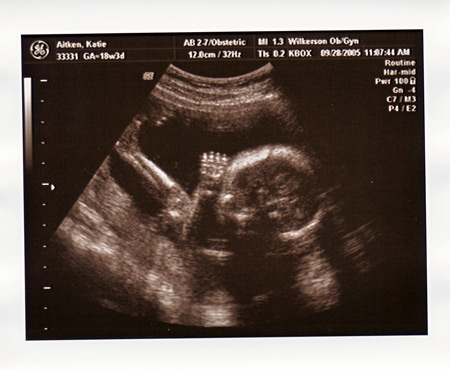

I had my ultrasound today, and found out everything is perfect and in place. We are so excited that Maeve will have a little sister to play with!!!